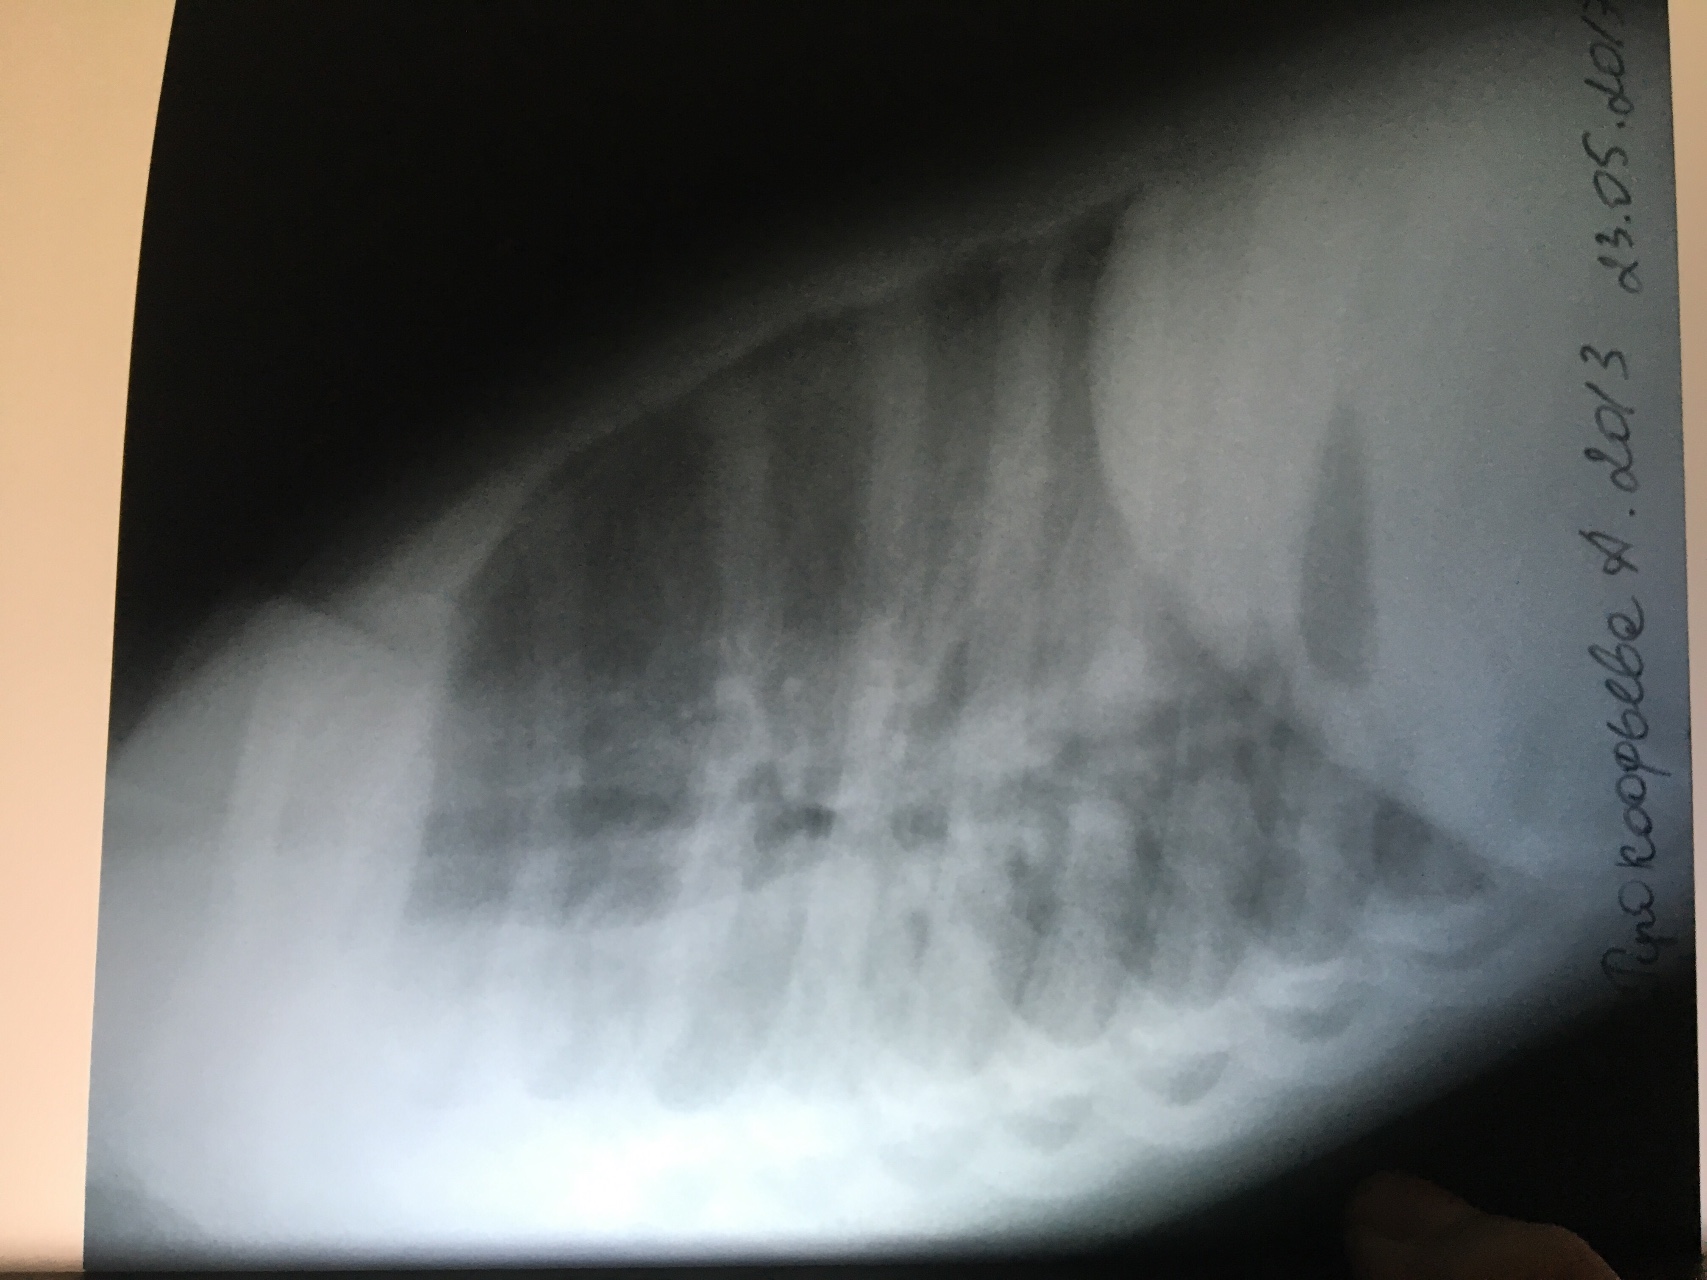

Острая внебольничная пневмония по МКБ-10: признаки и примеры